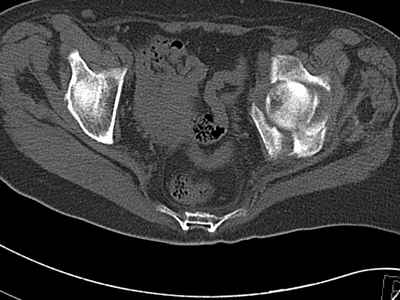

Уважаемые коллеги, возник вопрос по лечению нашей пациентки 60 лет. Около года назад множественная травма: в том числе Т-образный перелом вертлужной впадины. На сегодняшний день сращение отломков имеется на ограниченных участках, имеется дефект задней колонны вертлужной впадины. Движения неплохие, ходит с костылями, приступая на ногу. По мнению эдопротезистов при установке антипротрузионного кольца или октопуса не хватит костного материала и необходимо перед протезированием выполнить реконструкцию впадины, иначе чашка протеза неминуемо выпадет.Просьбы поделиться положительным и отрицательным опытом протезирования в подобных случаях.Возможно ли обойтись без реконструкции?Или лучше с ней?С уважением РАВ.